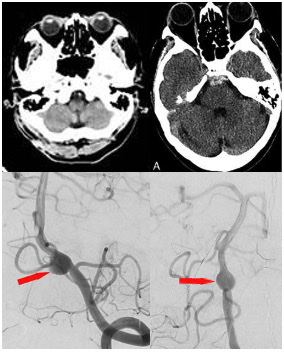

2024 B35  【問題】50代女性。頭痛で単純CT撮影(図1)した。1年後に左上下肢感覚障害で受診し、単純CT撮影(図2)、その際の左椎骨血管撮影(図3)を示す。行うべき治療を1つ選べ。

OA-PICA bypass+左椎骨動脈trapping

• 31

2023 B36 【問題】40代女性。クモ膜下出血で搬送。以下の動脈瘤を認め、バルーンアシスト下でのコイル塞栓術を施行した。治療前、治療後の画像を示す。(左内頚動脈撮影、左前斜位) 対応は何か。2つ選べ。